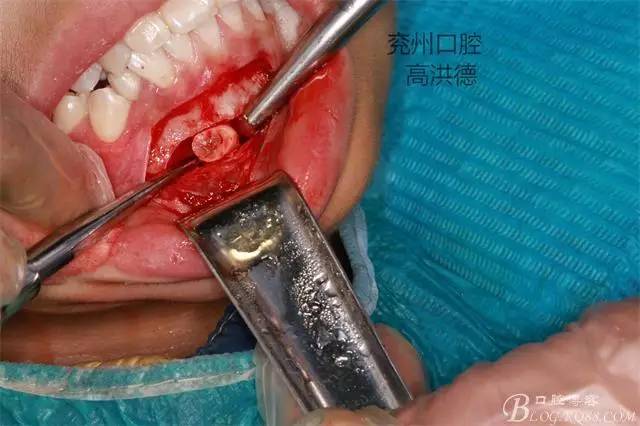

暴露牙齒中端

按設(shè)計(jì)截?cái)嘌例X